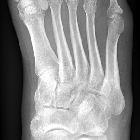

Sesambeine des Fußes

Os

sesamoideum hallucis multipartum. Es lassen sich 4 getrennte Knochenkerne des medialen Sesambeins am Metatarsale-I-Köpfchen identifizieren.